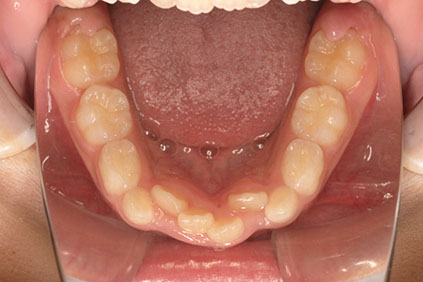

右上の前歯が生えてこない事を気にされ来院されました。 レントゲン写真から、上顎正中に過剰歯が埋伏していることが原因でしたので、抜歯して経過観察。 遅れて、無事に生えてきました。 もし、自然に生えてこない場合は、開窓して、引っぱり出します。(廷出) 状態により、引っぱり出せない場合もあります。 将来的にスペース不足により、上下顎前臼歯部に重度の叢生(がたつき)が予測できますので、がたつきを減らすために、小児矯正で側方拡大を行いました。 小児矯正で側方拡大を行ってもスペースが足りない場合(著しくスペース不足の場合)は、がたつき(叢生、八重歯)が残ります。 残ったがたつき(叢生)は、本格矯正ですべて生え変わった中学生から治せば問題ありません。 来院間隔が平均で1.5カ月でしたので半年ほど治療期間が長いです。